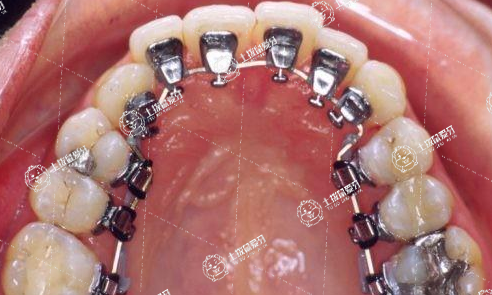

5、舌側(cè)矯正

舌側(cè)矯正

舌側(cè)牙套按照患者牙面的不同情況進(jìn)行精確設(shè)計(jì),定位精度比較高。

價(jià)格:最貴,費(fèi)用是一般牙套的2-3倍;

美觀度高:粘在牙齒內(nèi)側(cè),表面看不出戴了牙套;

舒適度差:牙套在舌側(cè)不舒服,剛開始還可能出現(xiàn)大舌頭說話的情況。